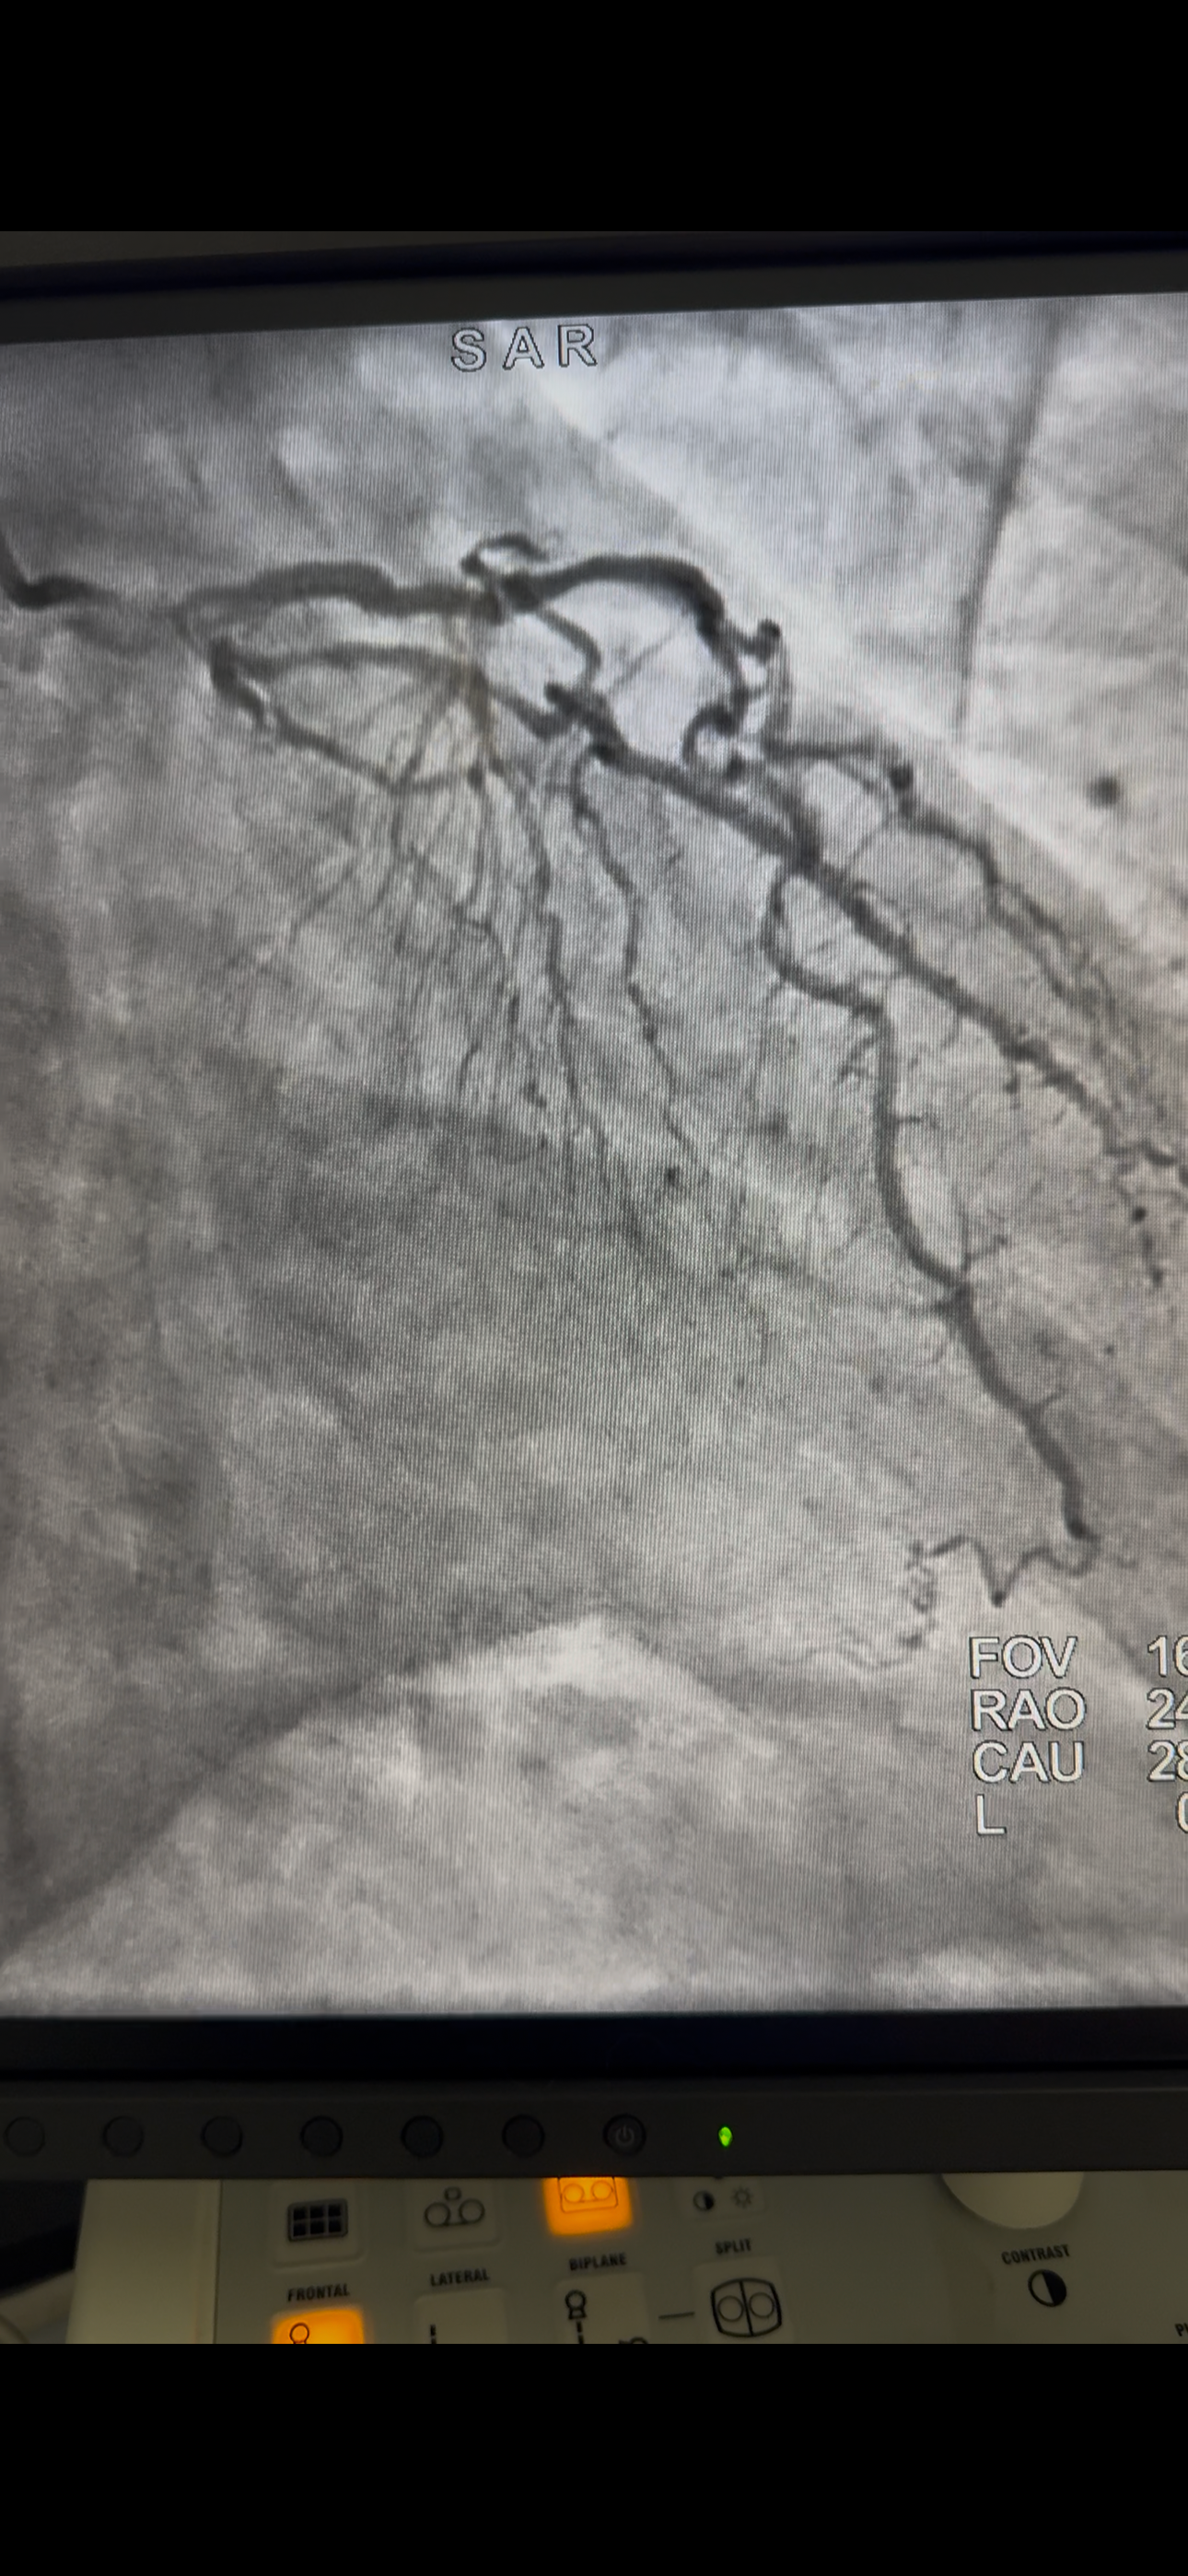

Hola a todos, espero que se encuentren bien. Quiero pedir su apoyo de corazón, ya que mi papá se sometio una cirugía a corazón abierto. Fue un procedimiento urgente y los gastos hospitalarios son muy elevados.